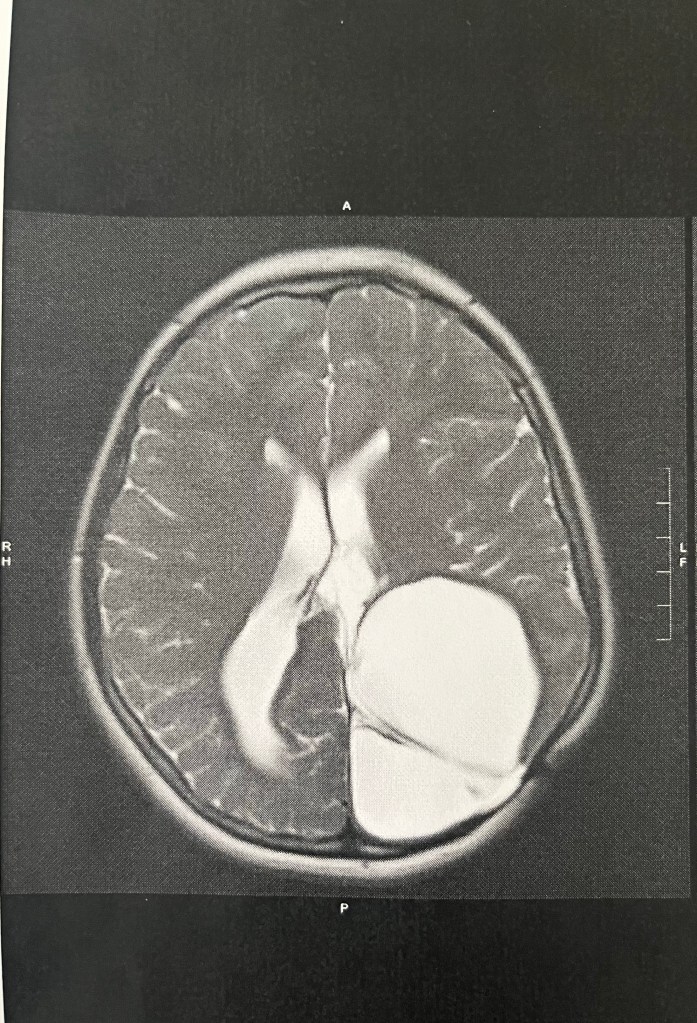

However, stable wasn’t what I had my hope set on today, and I caught myself staring at this image of Harper’s brain on the way home, trying not to be disappointed that everything has remained the same and not gotten smaller. The doctor has never indicated that we should see a decrease, but I pray for it anyway, wanting to see that physical miracle… and today wasn’t the day.

As I was staring at that massive brain cyst today, the Lord reminded me that I wasn’t staring at an unanswered prayer. I was looking at a miracle.

That large white mass taking up the back corner of Harper’s brain? The white enlarged ventricles due to extra fluid and another cyst in the center of her brain? The not-so-straight midline? All evidence of a miracle. A testimony of His goodness. Because even with all of that, my child walks. She talks. She sees and she hears. She reads and writes. She plays and imagines. She sings and dances. She loves. She lives.